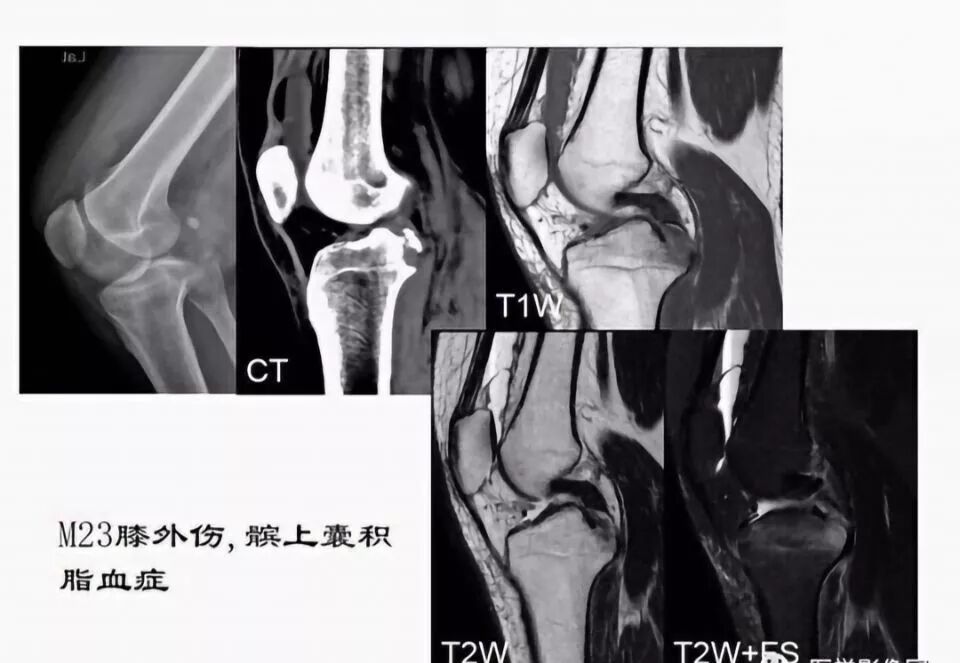

滑囊是关节囊外的囊性结构,可与关节囊相通,其作用是减少肌腱、骨和皮肤之间的摩擦。可以分为先天性滑囊和获得性滑囊。